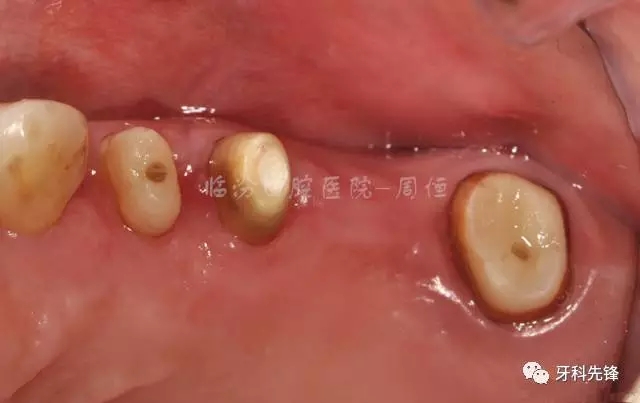

圖3 術(shù)前頜面照

檢查:15 16 17 烤瓷冠修復(fù)體,崩瓷,邊緣不密合,食物嵌塞,齦下牙石II°,冷熱診無不適,叩診(+),牙齦輕微紅腫。

14  殘冠,位于齦下2mm,牙齦顏色正常,叩診(-)